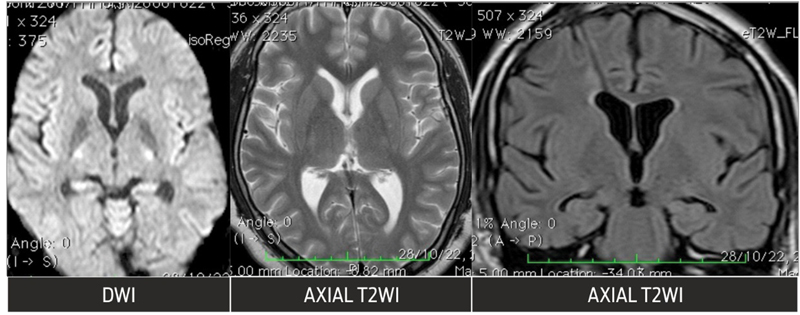

A 26-year-old man with a history of the consanguineous marriage of parents presented with somnolence, ataxia, and forgetfulness for a duration of 4 weeks, which was progressing. His medical history included a diagnosis of Crigler–Najjar syndrome, type II, and on examination icterus was present with vital signs being in the normal range. Magnetic resonance imaging (MRI) scan of the brain demonstrated a lesion in the bilateral medial thalami extending along the posterior wall of the third ventricle and proximal aqueduct of Sylvius measuring 2.7 × 1.8 × 2.5 cm with mild perilesional edema ([Fig. 1]). This was followed by an endoscopic third ventriculostomy and a biopsy of the space-occupying lesion, which was suggestive of diffuse B-cell lymphoma of the CNS. No atypical or malignant cells were detected on cerebrospinal fluid cytology. Whole-body positron emission tomography–computed tomography (PET-CT) scan was done to exclude systemic diffuse large B-cell lymphoma.

| Fig 1 :Pretreatment MRI shows mass lesion in the region of the third ventricle with involvement of bilateral thalami, with perilesional edema in the thalami showing restricted diffusion with diffuse T2, fluid-attenuated inversion recovery (FLAIR) hyperintensity, and postcontrast enhancement and dilatation of the lateral ventricles with periventricular hyperintensity.